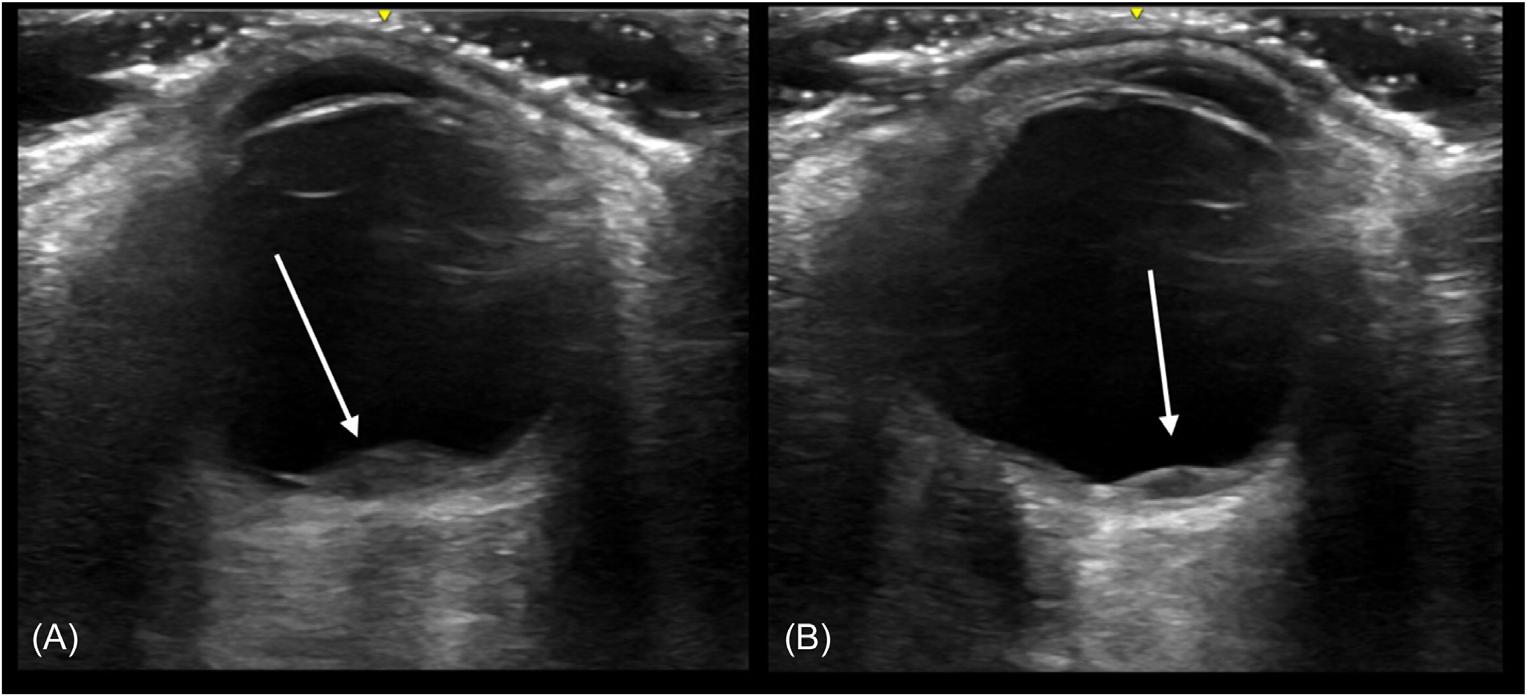

298 Point-of-care Ultrasound Diagnosed Intraocular Breast Metastasis

Hamzah M. Yusuf, Timothy Batchelor, Nicholas Ashenburg